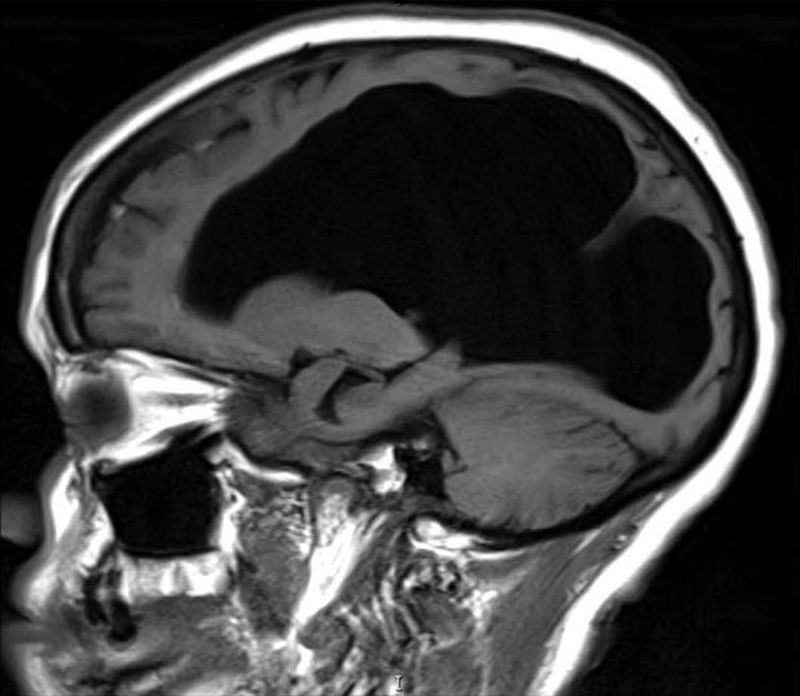

A 62-year-old woman was found unresponsive and the following MRI scan was obtained. No previous images are available for comparison. Which cause for the image abnormality is unlikely? A) Cerebral aqueduct stenosis B) Meningitis C) Alzheimer's disease D) Traumatic brain injury

Cerebral aqueduct stenosis is uncommn at that age....may be menigitis ,which cause exudates ,,which would have blocked the aqueductbcausing dilatation of ventricles